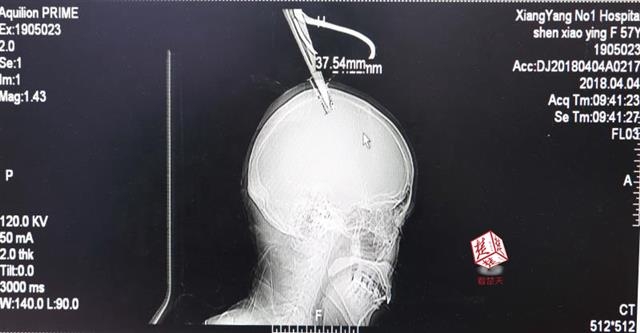

醫(yī)生檢查發(fā)現(xiàn),剪刀刀尖斜嵌在沈某顱骨里,離腦髓只有兩三毫米。所幸是斜著插進(jìn)去,如果是垂直刺入,很有可能造成癱瘓。

4月4日清晨,襄陽(yáng)市樊城區(qū)太平店鎮(zhèn)57歲的農(nóng)村婦女沈某,在采摘香椿嫩芽時(shí),綁在竹桿上的剪刀因竹子腐朽不慎折斷,剪刀斜插入頭顱。經(jīng)過及時(shí)搶救,目前脫離生命危險(xiǎn)。

醫(yī)生檢查發(fā)現(xiàn),剪刀刀尖斜嵌在沈某顱骨里,離腦髓只有兩三毫米。所幸是斜著插進(jìn)去,如果是垂直刺入,很有可能造成癱瘓。最終經(jīng)過手術(shù),剪刀被取出,沈某目前仍在ICU進(jìn)一步觀察。